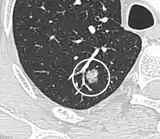

• Location: Upper lobe location is a risk factor for cancer, while a location close to a fissure or the pleura indicates a benign lymph node,[8] especially if having a triangular shape.[9]

• Margin morphology: a spiculated margin is a risk factor for cancer.[8] Benign causes tend to have a well defined border, whereas lobulated lesions or those with an irregular margin extending into the neighbouring tissue tend to be malignant.[10] In particular, spiculations are highly predictive of malignancy with a positive predictive value up to 90%.[9] Also, a "notch sign", which is an abrupt indentation of the nodule, increases the risk of cancer, but may also be found in granulomatous diseases.[9]

Calcifications and popcorn-like appearance, conferring a diagnosis of hamartoma.[9]

• In case of calcifications, a popcorn-like appearance indicates a hamartoma, which is benign.[3]

• Pleural retraction is far more common in cancers.[9] It is the pulling of visceral pleura towards the nodule.[9]

Lung nodule abutting a pulmonary cyst.[9]

• A lung nodule abutting a pulmonary cyst is a rare finding, yet indicating cancer.[9]

• Bubble-like lucencies in the nodule indicate cancer:[9]

Thin slice and maximal intensity projection of a lung nodule, the latter better visualizing vascular convergence.[9]

• Vascular convergence is where vessels converge to a nodule without adjoining or contacting the edge of the nodule, and is mainly seen in peripheral subsolid lung cancers.[9] It reflects angiogenesis.[9]